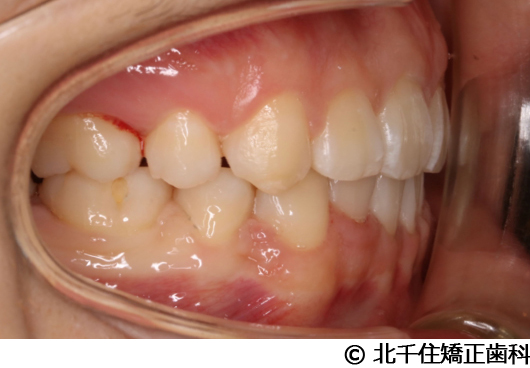

【症例3】叢生

- 治療前

- 治療後

- 治療名

- 叢生

- 費用

- 1,125,000円(税込)

- 期間

- 2年1ヵ月

- 治療回数

- 26回

- 通院頻度

- 1ヵ月ごと

- 年齢・性別

- 19歳3ヵ月・女性(初診時)

主訴:デコボコ、口元の突出

上下顎第一小臼歯4本を抜歯してワイヤー矯正(セラミックブラケット)。

叢生に対し抜歯を併用した矯正治療により、歯列および咬合関係の調整を行った症例である。治療後は保定装置を使用し、歯列および咬合の安定維持を目的として定期的な経過観察を行っている。